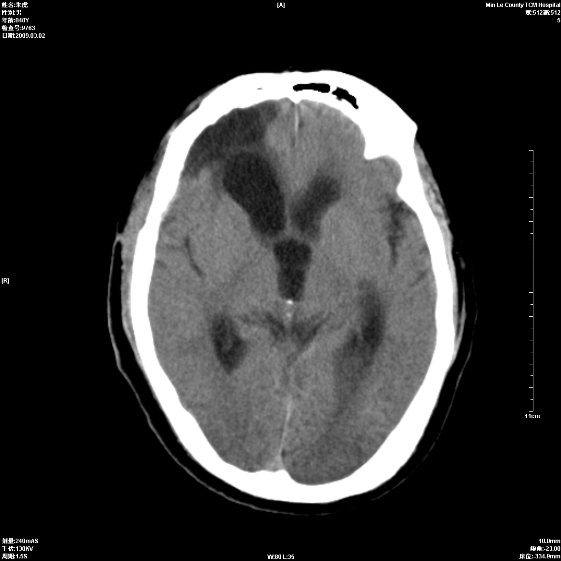

标题: CT18444:男颅咽瘤术后一月复查脑积水增多 [打印本页]

标题: CT18444:男颅咽瘤术后一月复查脑积水增多

右侧额叶局软化灶,梗阻性脑积水。

右额叶软化灶。梗阻性脑积水。

手术后改变

1、右额叶脑软化

2、脑积水

1)右侧额颞部颅骨术后改变。2)右侧额颞叶脑软化灶。3)脑积水(梗阻性)。

手术后改变1、右额叶脑软化2、梗阻性脑积水。